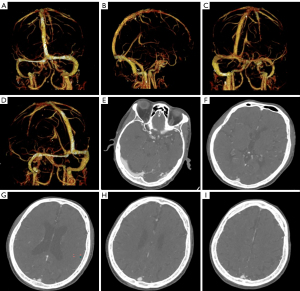

Laboratory tests revealed a white blood cell count of 14.3×109/L, of which, eosinophils accounted for 47.4% (absolute value: 6.76×109/L), and a platelet count of 64×109/L. An emergency triple head computed tomography (CT) [plain scan + computed tomography angiography (CTA) + computed tomography perfusion (CTP)] ruled out hemorrhage and major vascular lesions (Figures 1,2). Upon admission, the patient reported a 15-hour history of symptoms, exceeding the standard 4.5-hour time window for intravenous thrombolysis (IVT) as per the American Heart Association/American Stroke Association guidelines (13). Additionally, the laboratory results revealed a platelet count of 64×109/L, which further contraindicated IVT due to an increased risk of bleeding. Head CTA and CTP excluded large-vessel occlusion, and thrombocytopenia necessitated cautious anticoagulation strategies over thrombolytic therapy.

The patient’s response to corticosteroids and durable remission further supported a diagnosis of idiopathic HES (28). Notably, while emergency triple head CT (plain scan + CTA + CTP) revealed no large-vessel occlusion or perfusion abnormalities, subsequent MRI confirmed an acute infarction in the basal ganglia, showing that eosinophil-mediated microvascular embolism may evade detection on routine imaging (29). The imaging-clinical discrepancy suggests a unique “biphasic pattern” in eosinophil-related cerebral infarction, characterized by direct blood-brain barrier disruption via eosinophil granule proteins and microcirculatory disturbances from the release of procoagulant substances like tissue factor and plasminogen activator inhibitor-1 (30). This observation provides two key clinical insights: (I) negative CTA results do not exclude idiopathic HES-related cerebral infarction, requiring close monitoring for distal microvascular embolism induced by eosinophil microparticles; and (II) eosinophil-derived extracellular traps, forming a “thromboinflammatory network” via NETosis can sustain thrombosis even with normal vascular imaging (31).